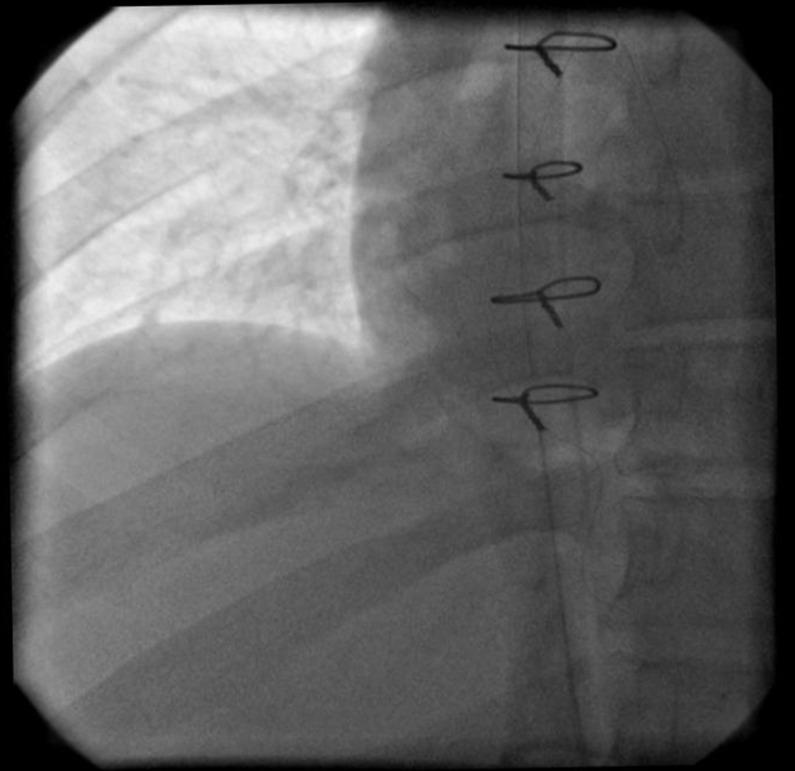

交通事故后肝上型下腔静脉及右心房血栓形成

Supra hepatic inferior vena cava and right atrial thrombosis following a traffic car crash.

We present a case of nephrotic syndrome associated with right atrial and supra hepatic vein part of inferior vena caval thrombosis. This patient presented with dyspena, lower extremity edema and back pain after a vehicle accident and blunt trauma to the abdomen. Trauma should be considered not only as a thrombophilic pre-disposition, but also as a predisposing factor to IVC endothelium injury and thrombosis formation. Echocardiography revealed supra hepatic vein IVC thrombosis floating to the right atrium. A C-T scan with contrast also showed pulmonary artery emboli to the left upper lobe. With open heart surgery, the right atrial and IVC clot were extracted and the main left and right pulmonary arteries were evaluated for possible clot lodging. The patient had an uneventful postoperative recovery and thrombosis has not reoccurred with periodical follow-up examinations.

摘要

我们报告一例肾病综合征合并右心房及下腔静脉肝上段血栓形成的病例。该患者在车祸及腹部钝性创伤后出现呼吸困难、下肢水肿和背痛。创伤不仅应被视为血栓形成的易患因素,还应被视为下腔静脉内皮损伤和血栓形成的诱发因素。超声心动图显示肝上段下腔静脉血栓漂浮至右心房。增强CT扫描还显示左上叶肺动脉栓塞。通过心脏直视手术,取出右心房和下腔静脉内的血栓,并评估左右主肺动脉是否有血栓栓塞。患者术后恢复顺利,定期随访检查未再发生血栓形成。